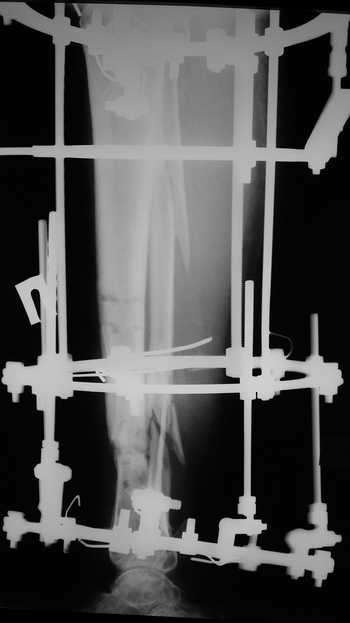

Женщина 46 лет, неудачно лечившаяся по поводу перелома голени в нижней 1\3 сначала в гипсе, поступила через 6 месяцев после остеосинтеза пластиной (рис 1). Имелась деформация в нижней 1\3 голени: варус, антекурвация, наружная ротация, два свища. Удалена пластина, дебридмент мягких тканей,

остеотомия м\б кости, аппарат Илизарова. По рентгенограммам в двух проекциях произведено планирование устранения смещений (рис 2 и 3), между вторым и третьим кольцом установлены 6 телескопических дистракторов Гесапода, данные введены в программу, и далее втечение 10 дней больная подкручивала телескопы согласно выданной компьютером инструкции. По завершению репозиции гексаподные телескопы обратно заменены на обычные штанги от аппарата Илизарова (рис 4 и 5). Еще через две недели забит гвоздь (рис 6, контроль

через 4 месяца).